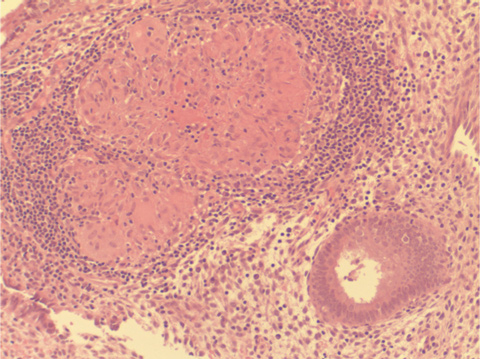

The child’s mother had no significant medical history apart from infertility. Infertility investigations had included ultrasound, hysteroscopy and diagnostic laparoscopy. A uterine curettage (as part of the work-up for infertility) 5 years before the pregnancy had shown “granulomas” in the endometrium (Box 2), but stains for acid-fast bacilli were negative. Culture for M. tuberculosis had not been performed at the time. Following the diagnosis of tuberculosis (TB) in her child, an interferon-gamma release assay (IGRA [QuantiFERON-TB Gold, Cellestis, Melbourne, Vic]) was performed, and gave a positive result. Chest x-ray revealed old fibrotic changes in the right upper lung, but no evidence of active tuberculous disease. She was prescribed antituberculous medication.

In 1994, criteria for diagnosis of congenital TB were revised.3 They comprise documentation of tuberculous lesions in the infant and one or more of the following: lesions in the first weeks of life; a primary hepatic complex or caseating granuloma; documented tuberculous infection of the endometrium or placenta; or exclusion of the possibility of postnatal transmission by investigation of close contacts. Our patient met the criteria for congenital TB: he had tuberculous lesions in early life; his mother had documented granulomas of the endometrium; and extensive contact tracing found no evidence of transmission to the child from other close contacts. Confirmation of endometrial TB in the mother, by repeat endometrial biopsy with PCR and culture for TB, would have been ideal, but would not have altered management in either the mother or the neonate. Thus, it was elected to treat the mother on the basis of the neonate’s culture results, rather than subject her to another procedure.